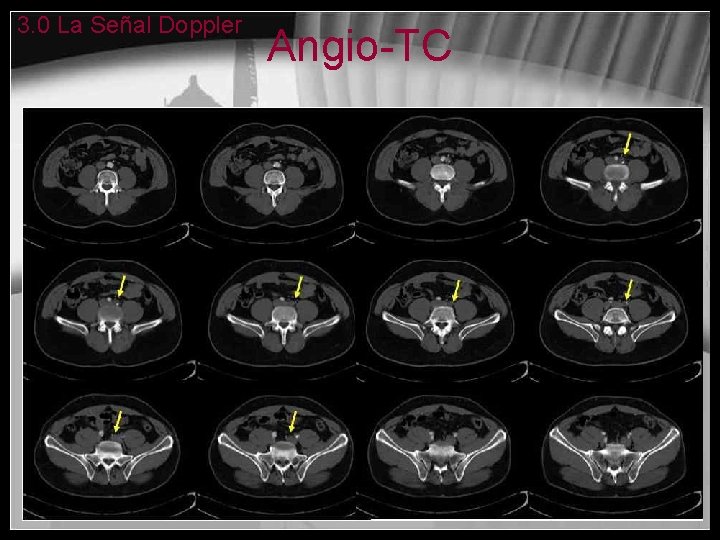

Trombosis de la Arteria Femoral Derecha: correlación Eco Doppler-Angio. TC Pierna derecha • El flujo es normal en la arteria femoral derecha Pierna izquierda • En la arteria femoral izquierda hay una pérdida del flujo trifásico. Distalmente el flujo es parvus-tardus.

3. 0 La Señal Doppler Angio-TC